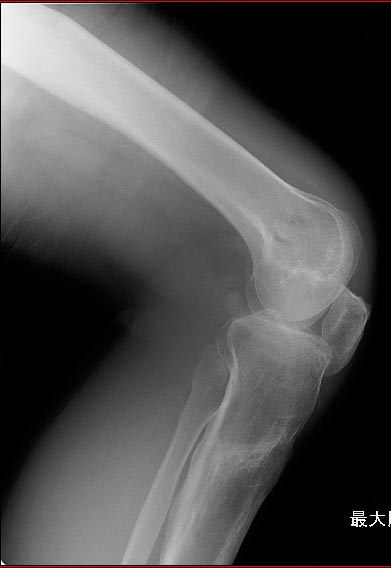

patella baja

Пациент 27 лет приехал для удлинения роста по эстетическим показаниям. Метод: крослатеральное двухэтапное удлинение голеней 4см и бедер 3 см.

Между этапами удлинения уезжал к себе домой в Японию на реабилитацию. Между этапами удлинения движения в коленных суставах разгибание полное сгибание 90-85. После выписки (февраль 2012) даны соответствующие указание постепенно возрастающей нагрузки и ЛФК коленных суставов.

В настоящий момент жалобы на ограничение сгибания в коленных суставах. Снимки прилагаются.

Вопрос: почему возникло такое осложнение? Поверьте приходилось удлинять намного больше, а тут всего на 3-4 см и такое осложнение на обеих конечностях у одного пациента?

Что можно сделать? У кого есть опыт лечения patella baja?